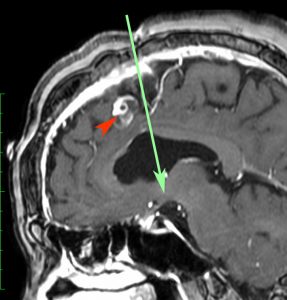

8歳で両側の視力低下が生じました。眼科では精神的なものと診断されて,4ヶ月くらいで右視力 0.4(耳側半盲),左指数弁となりました。のう胞性頭蓋咽頭腫で大きな骨化を伴うもので1月くらいの間に全盲になるかもと判断しました(失明寸前です)。

矢印の先に見えるように下垂体は正常の形態です。この画像から灰白隆起の左後方,乳頭体の前方が腫瘍発生母地ということがわかります。尿崩症もなく下垂体機能は正常です。経鼻的な内視鏡手術で腫瘍の大部分を摘出すれば下垂体機能は廃絶します。

とにかく失明を避けるために急いで経蝶形骨洞手術(transsphenoidal-transtuberculum sellae approach)で腫瘍のう胞の減圧をしました(緑の矢印の経路 by 函館中央病院加藤功先生)。その後に前頭開頭で腫瘍を全摘出しました(右側の画像)。尿崩症はでましたが下垂体前葉機能は正常です。

右視力 0.45,左明暗弁の視力が残りました。でももし,経鼻手術をしないでいきなり開頭すればおそらく全盲になっていた例です。